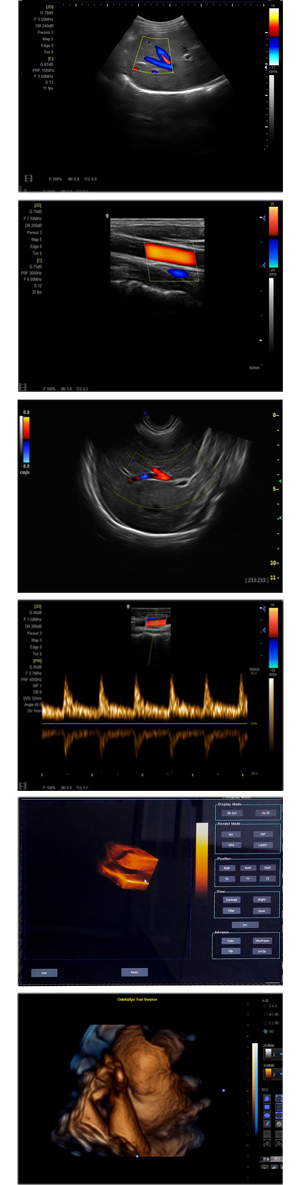

XF-7500型,秉承先鋒彩超技術(shù)之精華,擁有高雅大氣的獨特外型,為最新一代應(yīng)用型數(shù)字彩色多普勒診斷系統(tǒng),魅力與實力相融合??蓮V泛適用于腹部、婦產(chǎn)科、心臟、小器官、乳腺、肌骨及外周血管等諸多方面的診查,讓您在臨床超聲診斷應(yīng)用領(lǐng)域得心應(yīng)手,綻放異彩!

突破的成像技術(shù)

● 3D/ 4D成像技術(shù)/選配

● 應(yīng)用于腹部、腎臟、泌尿系統(tǒng)、產(chǎn)科、婦科、盆腔、大動脈、肌肉組織、小器官、乳腺、心臟等

● 能量多普勒成像(PDI)

● 彩色血流量圖(CDE)

● 脈沖頻譜多普勒成像(PW)

● 組織諧波成像技術(shù)